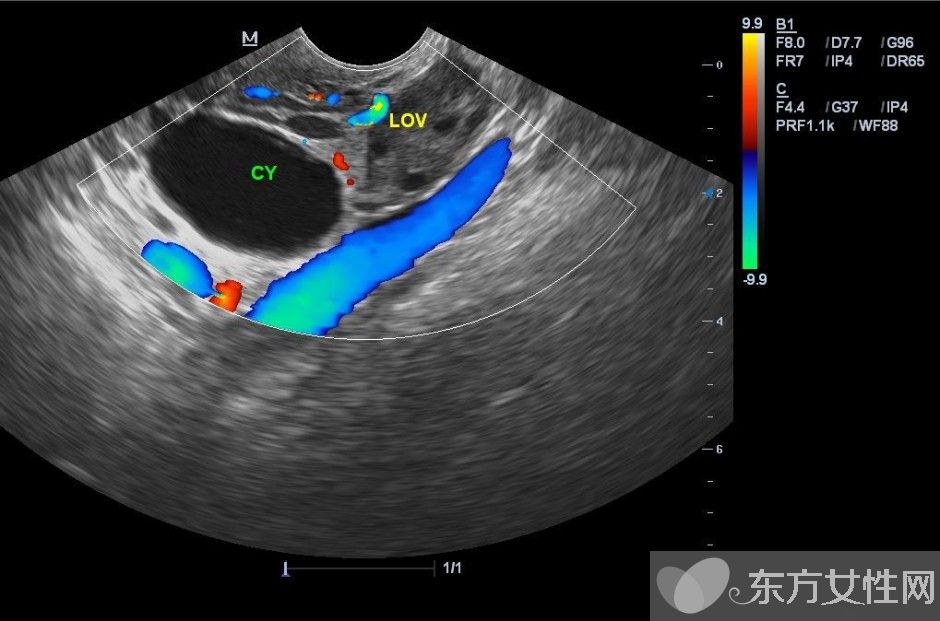

什么是卵巢囊肿?

卵巢囊肿是指卵巢上长出的囊性肿物,有各种不同的性质和形态,如单一型或混合型、一侧性或双侧性、囊性或实质性、良性或恶性。通常可分为两大类:

卵巢囊肿分为生理性和病理性两种,卵巢囊肿的症状有哪些?生理性的卵巢囊肿是在女性排卵期滤泡聚集而形成的,往往几个月后会自动消失。病理性的卵巢囊肿在早期也没有明显的症状,有症状者多表现为腹部疼痛、月经不调、白带异常、腹部肿块等,容易被忽视或误诊。